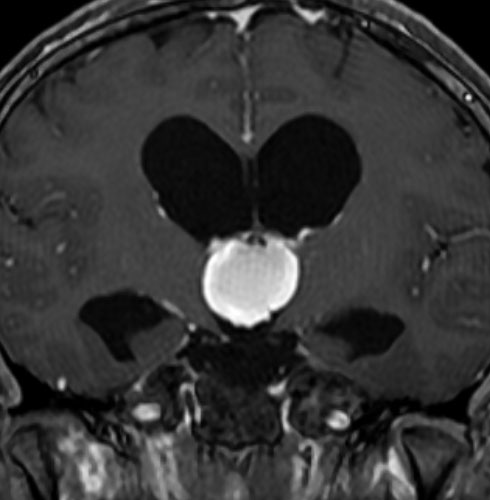

5歳の時に発見され23歳まで18年間経過観察をされてきた患者さんです。腫瘍はゆっくり,しかし確実に増大して,手術前には頭痛がひどく薬も効かず歩けなくなったという症状でした。術後に頭痛が無くなったので,のう胞による症状だったのでしょう。

下垂体柄の周囲にのう胞性腫瘍があります。T1強調画像では等信号,T2強調画像ではまだらな信号になっています。23年という長い経過から液状内容物が固形化したものと推定されます。T2で低信号となる部分があるのですが,黄色肉芽腫とは異なる像です。

下垂体柄は長く伸びています。のう胞による長期の圧迫のため斜台上部がerosionになって凹んでいます。トルコ鞍内の中間葉の位置に典型的な小さなラトケのう胞(黄色矢印)がみられますが,これは長年変化していませんでした。

左前頭側頭開頭 pterional approachで,のう胞壁を含めて完全摘出 complete removalしました。のう胞は下垂体柄の左側に付着してそこから発生したものでした。内容物は固体で寒天状のコロイドでした,一部軟らかくて一部は線維化していました。のう胞壁は半透明で薄い部分も線維性の膜状の部分もありました。病理検査では上皮細胞が証明されて内胚葉のう胞 endodermal cystの診断です。

ラトケのう胞はhiatusから内容液吸引だけして,皮膜はもちろんそのままにしています。